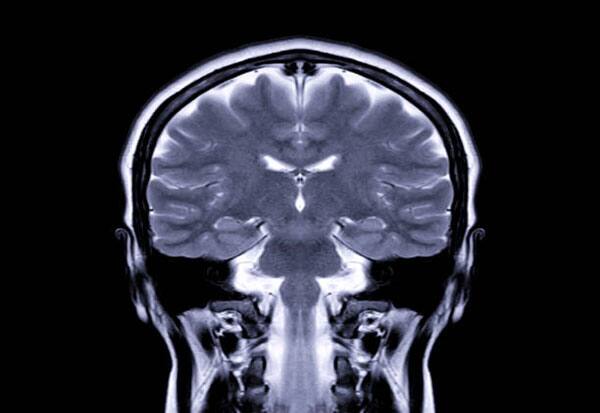

To better understand how humans evolved to become so skilled at thinking about what's happening in other peoples' minds, the team looked at fMRI brain scans of six people. Functional magnetic resonance imaging (fMRI) measures brain activity by detecting changes in blood oxygen levels.

"The results suggest that social cognitive functions emerge through coordinated activity between internal circuits of the amygdala and a broader distributed association network, and indicate the medial nucleus (located within the amygdala) may play an important role in social cognition in humans," authors wrote in the study published in the journal Science Advances.